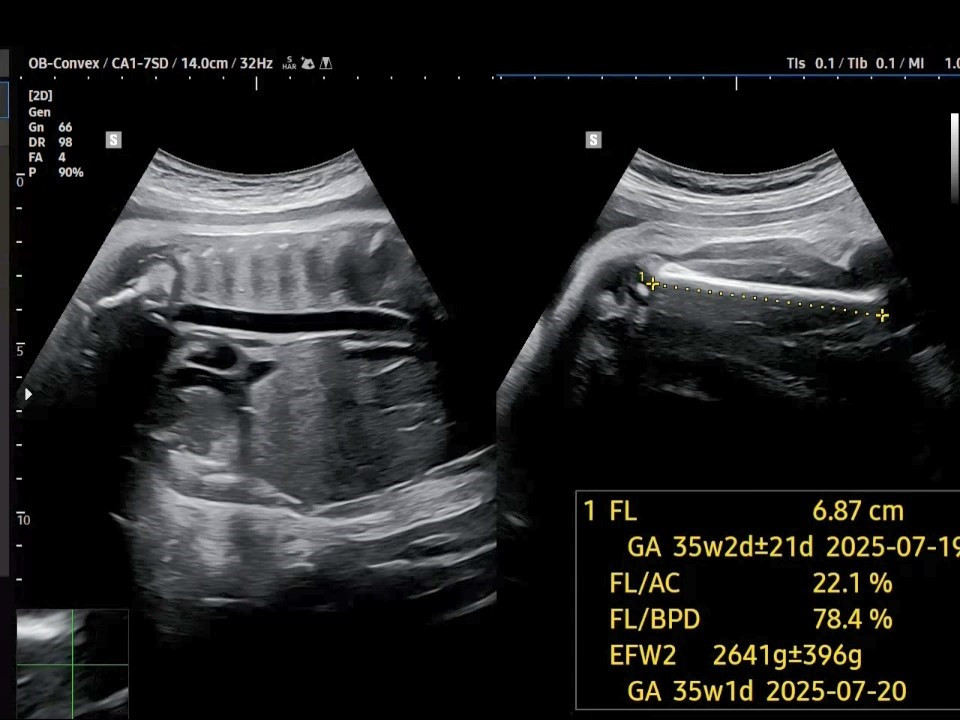

3. 허벅지 뼈의 길이(FL: Femur Length)는 6.87㎝로 지난주보다 0.1㎝ 가량 자랐습니다. 그리고 태아 추정 체중(EFW: Estimated Fetal Weight)은 약 2.6㎏으로 나옵니다. 지난주에 비해 약 100g 정도 몸무게가 늘기는 했는데, 막달에는 태아가 일주일에 약 200g씩 크는 것에 비해서는 잘 안 크고 있다고 보입니다.

38주 FL.jpg [38주 차 허벅지뼈 길이]